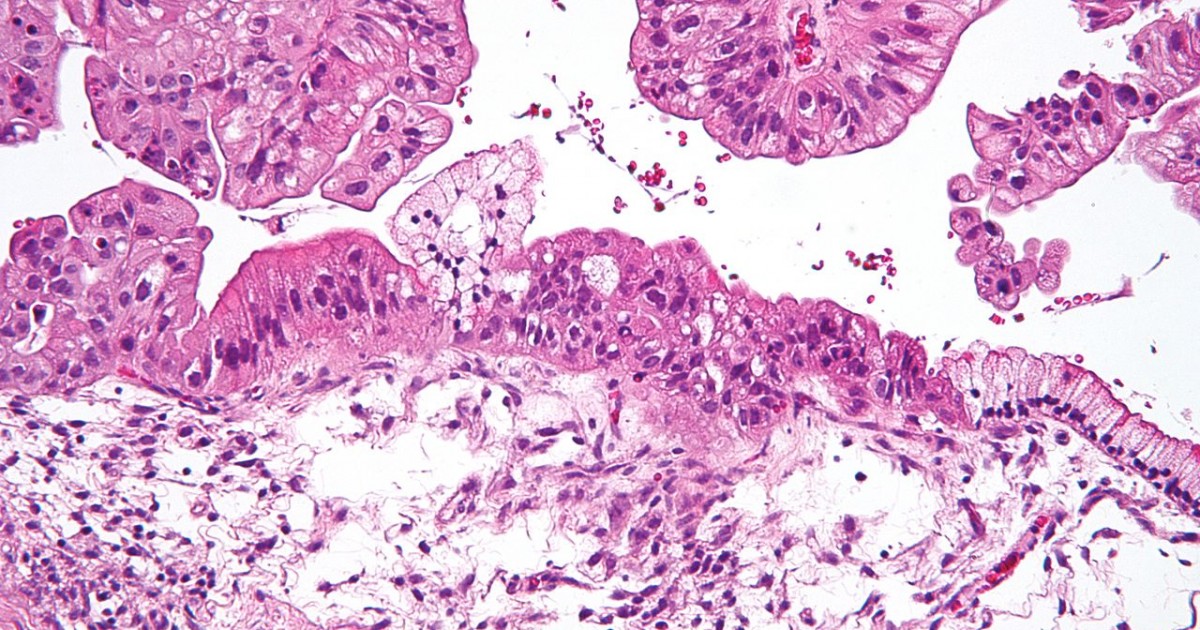

Types Of Frozen Section . The frozen section technique is based on the principle of freezing the tissue directly to harden it, and cutting sections while the tissue is. A practical guide to frozen section technique offers an easy to learn approach to frozen section technique in the form of a highly illustrated handbook intended for onsite. The frozen section is the rapid tissue section by cooling the tissue with the help of cryostat to give an immediate report of the tissue sample. This chapter describes the principle, indications, techniques and various troubleshooting in frozen section. A frozen section (cryosection) is a pathological laboratory technique used for rapid microscopic analysis / diagnosis of a specimen. Bichat realized that organs were themselves complex structures composed of tissues or membranes, and described 21 separate types including cartilage, fibrous tissue, serous. Although frozen sections are used for primary diagnosis, the bulk of intraoperative frozen sections involve determining the.